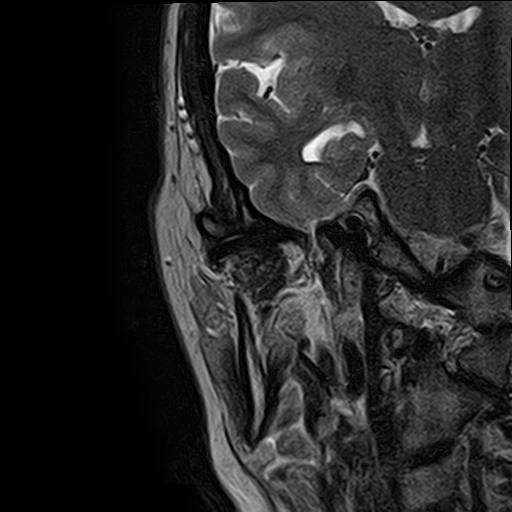

Чаще всего дисфункция височно-нижнечелюстного сустава обусловлена внутренним повреждением, смещением мениска и суставной головки нижней челюсти. Для определения степени смещения внутрисуставных структур выполняется функциональная проба с проведением МРТ в двух положениях:

• с закрытым ртом;

• с открытым ртом.

МРТ ВНЧС с капой включает в себя два протокола: с открытым ртом и с закрытым ртом. Данная функциональная проба позволяет проследить степень смещения внутрисуставных анатомических структур и оценить биомеханику движений в суставе.

Протокол МРТ ВНЧС предусматривает проведение исследования в двух положениях: с открытым ртом и закрытым ртом. Данная функциональная проба дает возможность оценить биомеханику работы височно-нижнечелюстного сустава.